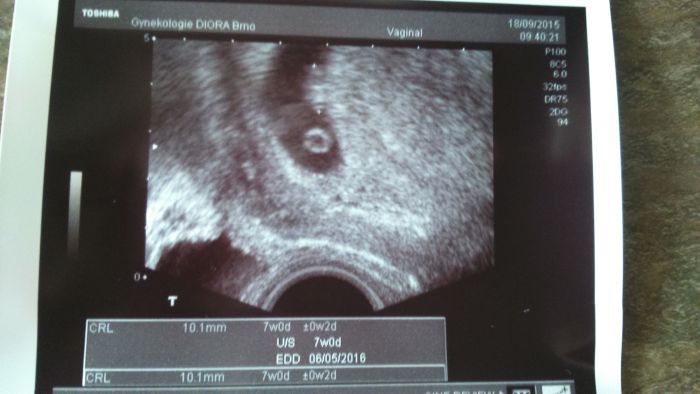

Tak my máme po kontrole,ale asi jsem měla posunutou ovu a tak jsme ještě mini:D ale jsme v deloze:) Na kontrolu jdeme 8.10 a pokud bude vše ok tak dostaneme prukazku:)